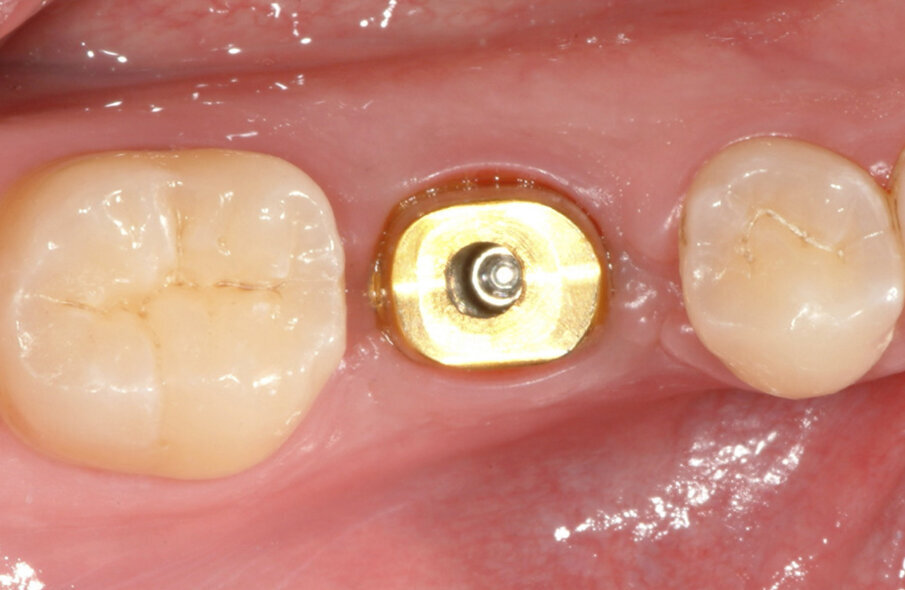

Fig. 10: The Atlantis abutment was virtually designed with the

emergence width of the replaced molar and manufactured in titanium with a titanium nitride coating.

Fig. 11: The Atlantis abutment in gold-shaded titanium, together

with the Atlantis abutment screw, was sent to the dental laboratory.